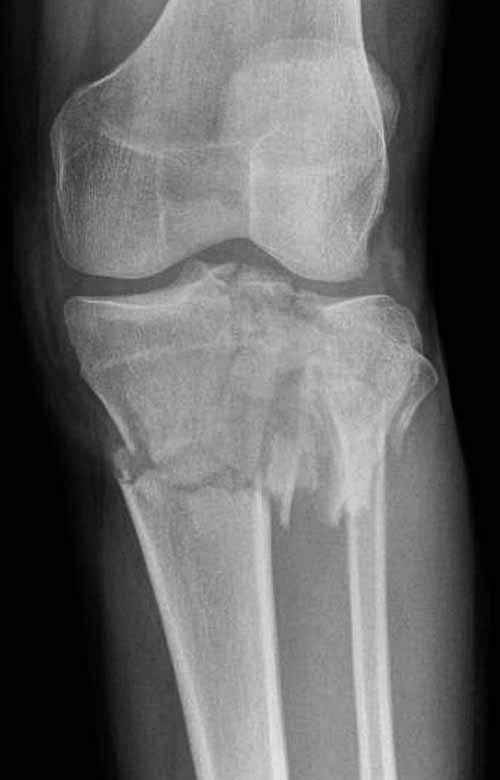

Двухколоннный перелом тибиал плато с вовлечением проксимального диафиза. Внутрисуставной компонент без смещения, и такой перелом можно лечить любым из описанных методов, о которых говорят наши коллеги.

Как понял, аппарат Илизарова не рассматривается предпочтительным для фиксации методом, хотя на фоне отека было бы идеальным для данного перелома. Для пластины требуется идеальная кожа, иначе наличие “суперсовременных имплантов” не поможет, и могут развиться серьезные осложнения.

В основном пластины рассчитаны на латеральную поверхность, потому что с латеральной стороны больше мягкотканая подушка, а также через латеральную колонну проходит ось конечности, что немаловажно в удержании оси от деформации.

Частая ошибка, когда фиксацию двух колонного перелома проводят одиночной пластиной, т.е с одной стороны, и такая фиксация не удерживает, происходит вторичноое смещение. Необходимо нейтрализовать второй пластиной или дополнительным наружным фиксатором.

Если у вас, кроме пластины, нет другого альтернативного варианта, тогда, учитывая мягкотканые проблемы с наружной стороны, я бы рекомендовал операцию делать в два этапа. Преимущества, сперва репозиция и фиксация перелома с медиальной стороны, а затем, после улучшения состояния мягких тканей, зафиксировать с латеральной стороны. Современные пластины имеют латеральный Jig для перкутанных мини доступов.

Кстати, коллеги правы для уточнения характера перелома надо делать Компьютерную Томографию.